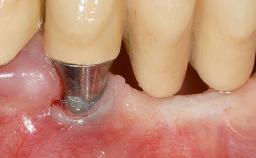

Connective-Tissue Graft to Increase the Width of the Keratinized Mucosa Around an Osseointegrated Implant

Adequate peri-implant soft-tissue thickness is essential not only for esthetic but also for functional reasons. In this case, Vincenzo Iorio Siciliano demonstrates how he achieved increased height and thickness of posterior peri-implant soft tissues to obtain a stable mucosal seal and a width of keratinized tissue favorable to toothbrushing.

The patient, a healthy 38-year-old woman, was referred for increasing the width of the keratinized tissues at the buccal aspect of dental implant 46. The site exhibited a premature-closure screw exposure caused by trauma during chewing, with inadequate keratinized tissue.